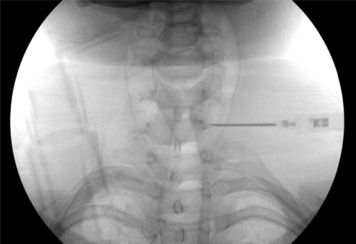

stellate ganglion Radiofrequency neurectomy is an advanced procedure which involves the precise placement of the Radiofrequency needle at the base of the uncinate process at C7 level and identification of the ganglion with the help of sensory and motor stimulation and then its targeted ablation using Radiofrequency current.

Whole procedure is done under local anaesthesia with some mild sedation.